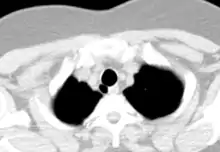

القصبة الهوائية أو الرُغامى (باللاتينية: Trachea) هي ممر يوجد في الجهاز التنفسي، ويحمل الهواء بين الرئتين والممرات التنفسية العليا. قطر القصبة الهوائية عند الإنسان 2.5 سم، وطوله 13 سم تقريباً. تنقسم القصبة الهوائية لنصفين، الأول يقع في العنق والآخر في الصدر. يوجد عدد من الغضاريف التي تساعد على الحفاظ على فتحة الرغامى. في النهاية تتشعب القصبة الهوائية لقصبتين رئيسيتن يذهب كل منهما إلى إحدى الرئتين حيث يصل الهواء.

يبلغ القطر الداخلي للقصبة الهوائية للإنسان حوالي 1.5 إلى 2 سم (0.6 إلى 0.8 بوصة) ويبلغ طولها حوالي 10 إلى 11 سم (4 بوصة). تبدأ عند قاع الحنجرة، وتنتهي عند سهم القَصّ، وهي النقطة التي تتفرع عندها القصبة الهوائية إلى القصبتين الرئيستين اليسرى واليمنى. تبدأ القصبة الهوائية في مستوى الفقرة العنقية السادسة، ويوجد سهم القص عند مستوى الفقرة الصدرية الخامسة (T5)، في مقابل الزاوية القصية ويمكن تموضعها حتى فقرتين أسفل أو أعلى، اعتمادًا على التنفس.

مقطع إكليلي من الحنجرة والجزء العلوي من القصبة الهوائية.